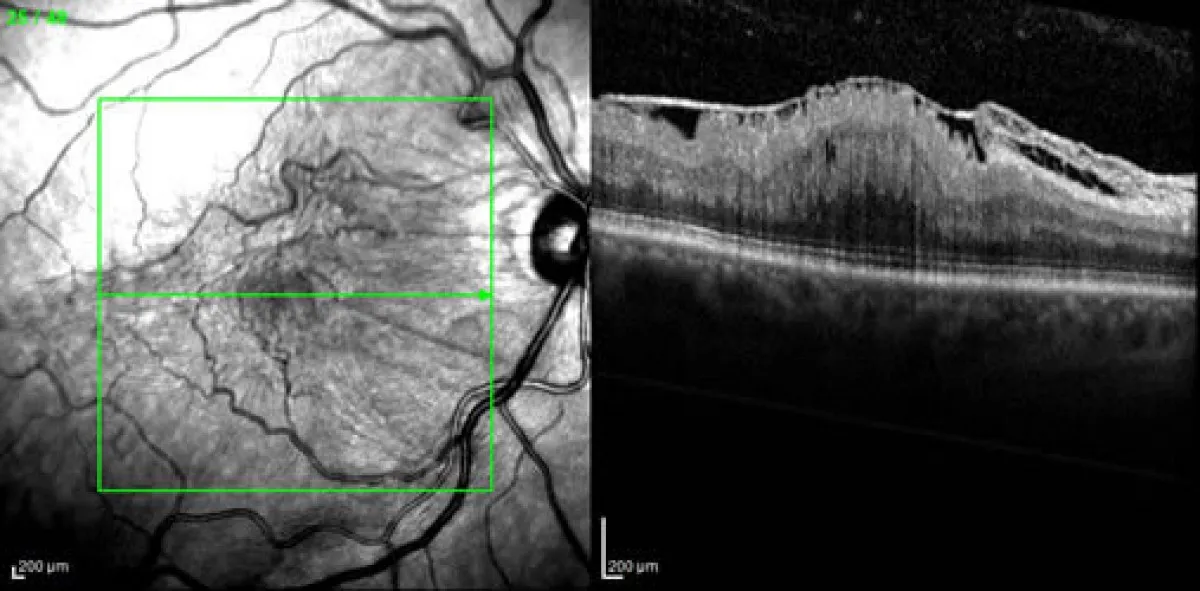

Διακρίνεται σε ωχροπάθεια δίκην σελοφάνης, η οποία είναι σχετικά ήπια και στην πιο σοβαρή μορφή της, τη ρυτίδωση της ωχράς (macula pucker).

B. Ρυτίδωση της ωχράς Αναφέρεται μεταμορφοψία και μείωση της κεντρικής οπτικής οξύτητας στα 5/10 ή και λιγότερο, ανάλογα με τη βαρύτητα.